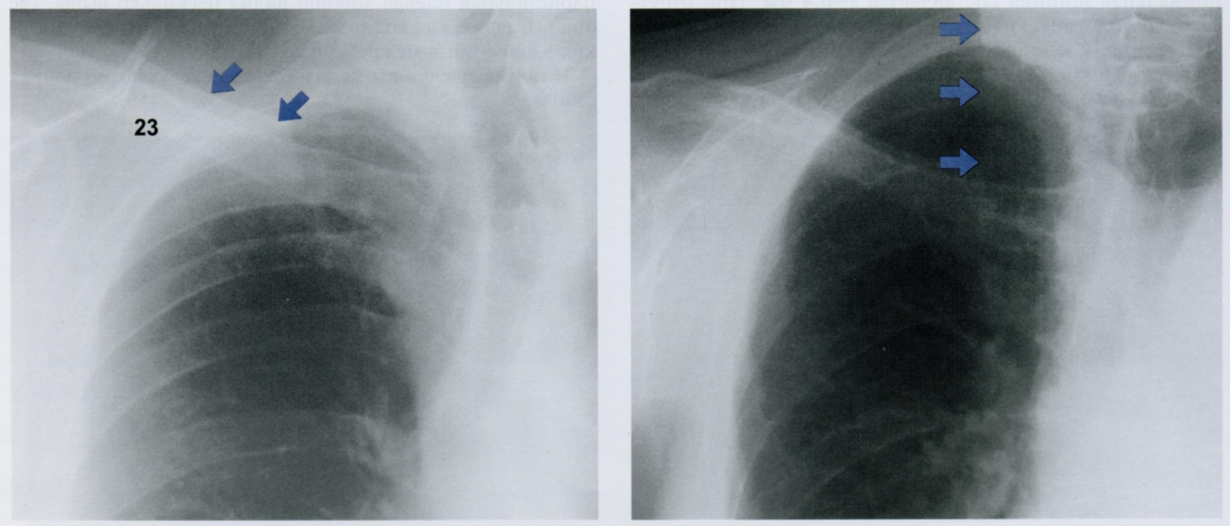

3

Оцените снимки.

Что отмечено стрелками? Мы можем это расценить как патологическое утолщение плевры?

На первом снимке затенение выше ключицы (косые стрелки) образовано складкой кожи над ключицей (23), поскольку складка расположена по касательной к направлению рентгеновского излучения. Эта тень не имеет никакого отношения к плевре. Чем больше глубина надключичной ямки, тем лучше видна эта тень.

На втором снимке определяется вертикальная линия на уровне купола правого легкого. Это нормальное рентгеновское изображение грудино-ключично-сосцевидной мышцы, край которой расположен по касательной к ходу рентгеновского излучения.

Будьте внимательны, чтобы не принять тень, сопровождающую ключицу, или вертикальную тень от грудино-ключично-сосцевидной мышцы за тень плевры.